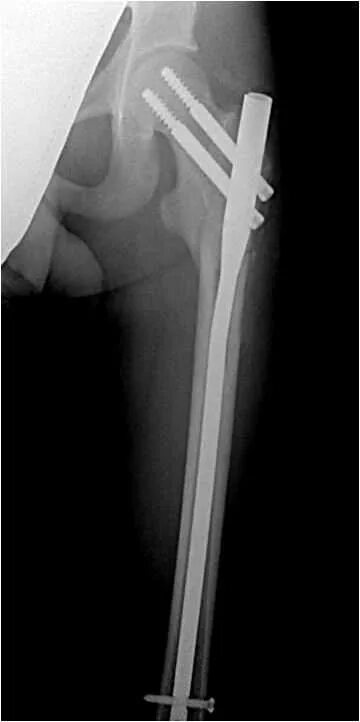

Остеосинтез чрезвертельного перелома